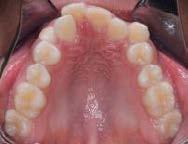

media superior, el overjet de 2 mm y un overbite del 20%, (Figura 6).

Se obtuvo clase I molar bilateral y clase I canina bilateral (Figura 7).

En las fotografías oclusales observamos la forma de arco oval, la solución del apiñamiento y el cierre de la mordida abierta. (Figura 8)

Extracción de primeros molares permanentes en la corrección de mordidas abiertas severas Figura 8. Oclusal superior e inferior. Figura 9. Sobreimposición.